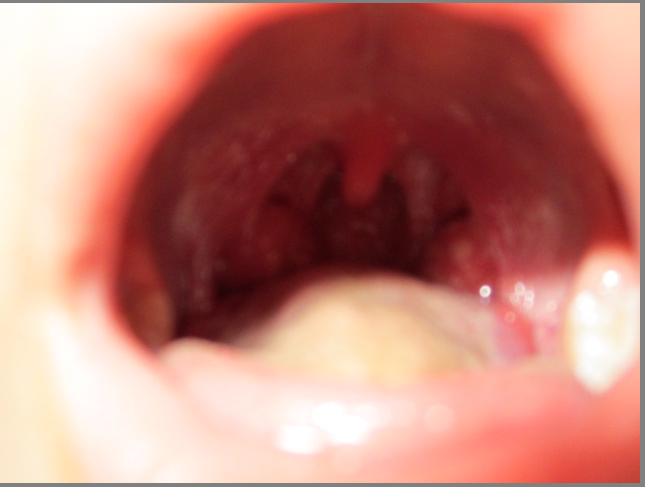

扁桃体脓苔全部消失